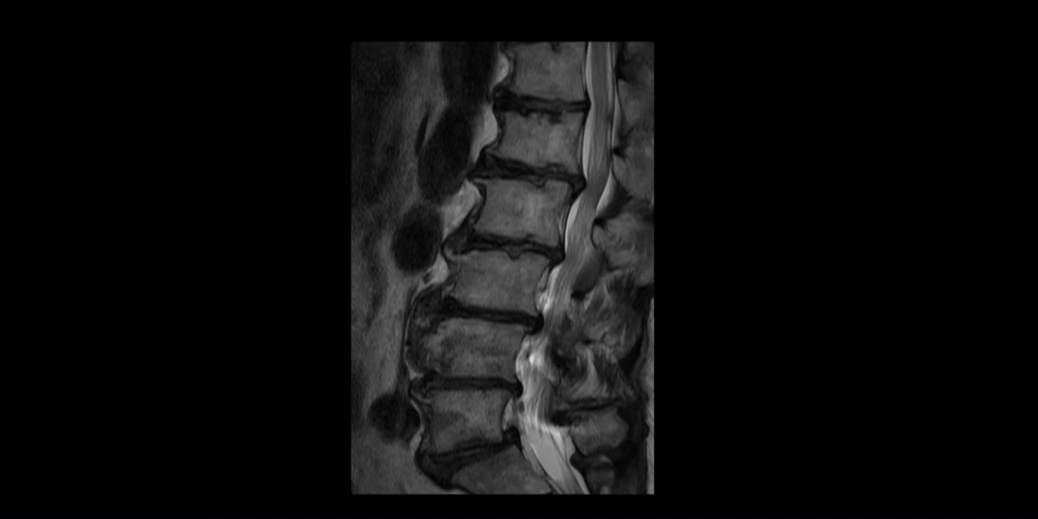

먼저 이분 MRI를 보면서 설명해 드린 후 이분 말씀 더 들어보겠습니다. MRI를 보시면 허리 5마디 전부가 퇴행이 심하고 안 좋습니다.

모든 마디에 중심성 협착

또는 추간공 협착이 있고

5번 1번에는 전방전위증이 있습니다.

그래서 대학병원에서도 다섯 마디 다 나사를 박아서 묶는 유합술을 하라고 권유한 겁니다.

이분의 이런 허리 퇴행 상태를 보면 아주 오랜 기간 허리가 아팠을 수밖에 없고 특히 오른쪽 신경가지가 빠져나가는 추간공이 많이 좁아져 있어서 오른쪽 다리가 심하게 저리고 아픕니다. 그런데 이렇게 여러 마디가 안 좋은 환자가 어떻게 수술 없이 치료가 가능할까요? 좁아진 신경 구멍을 수술로 넓혀야만 좋아지는 것 아닐까요? 전혀 그렇지 않습니다.